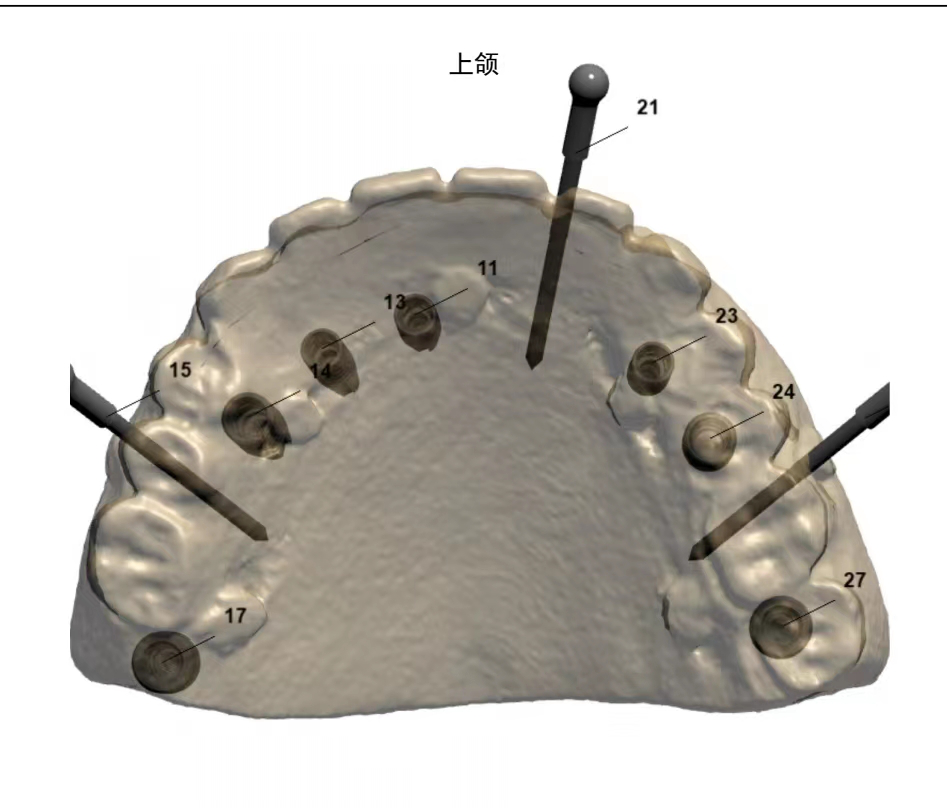

60岁的患者刘某(化名)因上颌牙列缺失数年要求种植牙修复,来到我院口腔科寻求种植方案。口腔科主任闫慧鑫接诊患者后,进行了系统检查及评估。为最大程度恢复患者牙齿功能,口腔科特邀北医三院口腔科副主任邹士琦会诊,根据CBCT影像检查结果进行三维重建和种植设计,最终确定了“种植后即刻义齿修复上颌牙列缺失”的治疗方案。

在征得患者及家属同意后,特邀北医三院口腔科副主任邹士琦来到延安,同延安分院口腔科主任闫慧鑫联合为患者开展了上颌种植牙。术中使用最新的士卓曼全程导板,局部麻醉后使用牙龈环切(术后不需要缝合),而非切开翻瓣,尽量减少创伤带来的不适,植入士卓曼种植体7颗,术后即刻修复恢复咀嚼功能,CBCT影像结果显示种植位点与术前设计位置一致,获得了患者的称赞。